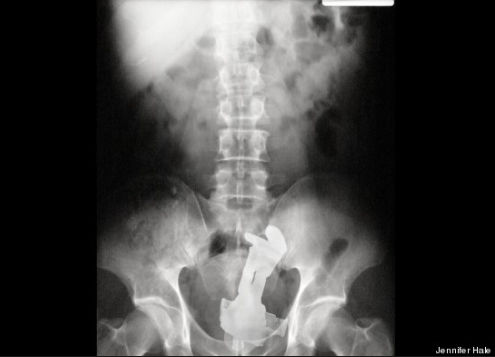

友人の看護師が送信してきたX線画像がテラオソロシイ。

メガネ。

救急救命室で働いてた頃、年に10~20人はこの手の患者が来た。

ビンやらスプーンやらなんでもかんでもって感じ。